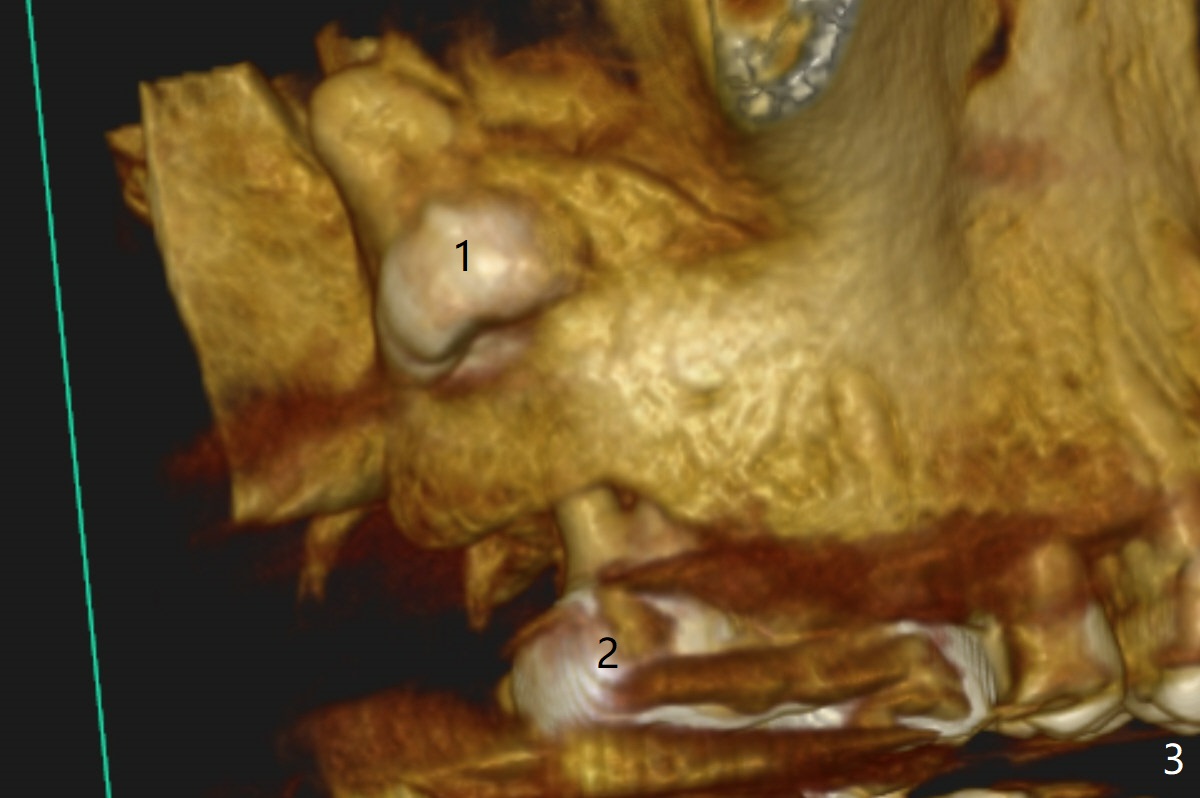

The tooth #1 should have been extracted buccodistally (Fig.3,4). Three or 4 months later, a 5x10 mm implant could be placed distopalatally superiorly to avoid removing the tooth #1 with ~ 1.5 mm clearance (Fig.5). To place an implant in orthopedic manner, the tooth #1 will be removed, while the implant should be longer (5x13 mm) to engage the bone superior to the socket of the tooth #1 (Fig.6).